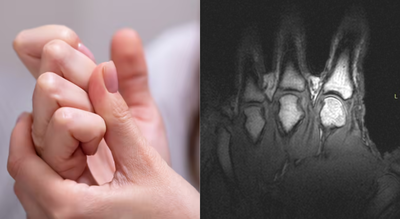

Researchers now agree that the sound produced when knuckles, toes or other joints crack is caused by gas, not bones grinding or cartilage snapping. A widely cited2015 studyused real-time MRI imaging to observe joints as they cracked, capturing the process as it happened rather than relying on theory alone.

Side by side MRIs revealing a gas bubble forming as joints in the fingers are cracked (University of Alberta)